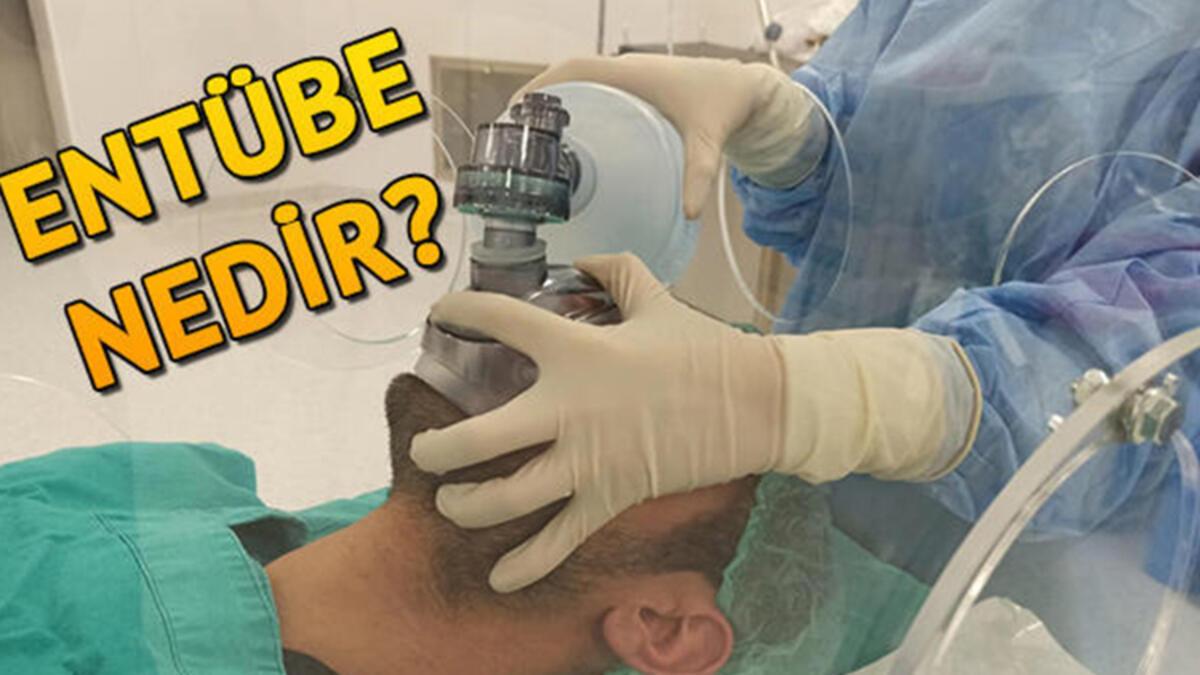

Entübe nedir, entübe hasta kimlere denir? Son Dakika Haber

Tıpta entübe ne anlama geliyor? Entübe hasta ne demek, ne kadar süre bu hastalar hayatta kalır